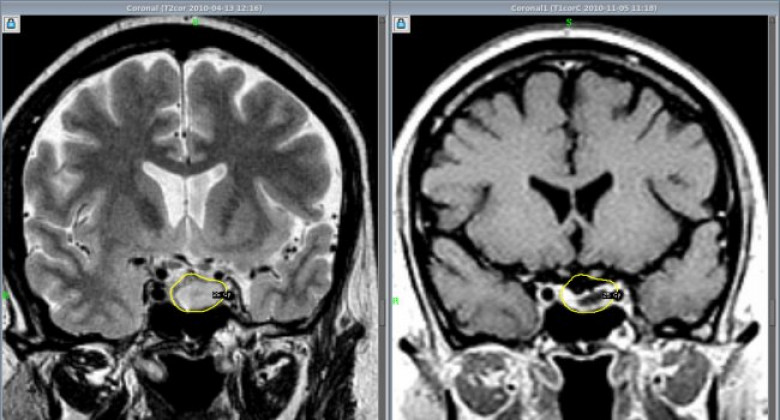

В МЦ «Астхик» сотрудничестве с благотворительным фондом «Вива» внедряют новый метод удаления аденом гипофиза

Аденома гипофиза – это доброкачественное новообразование, которое может крайне негативно сказываться на качестве жизни, вызывая нарушения со стороны эндокринной системы, а также нарушения зрения.

До недавних пор такие новообразования в МЦ «Астхик» удаляли с применением хирургического микроскопа. Теперь в медцентре внедряют и другой метод удаления аденом гипофиза – с помощью эндоскопа. Этот метод до недавних пор в Армении не применялся, и обучать ему специалистов в рамках одного из проектов благотворительного фонда «Вива» будет известный нейрохирург Вилен Азизян (Россия). В медицинском центре «Астхик» он уже провел три операции по удалению аденом гипофиза. Ассистировали ему армянские специалисты, которые в дальнейшем научатся проводить такие операции самостоятельно.

Аветис Киракосян, руководитель отделения нейрохирургии МЦ «Астхик», рассказал журналистам о том, что для внедрения эндоскопического метода удаления опухолей гипофиза был выбран медцентр «Астхик», так как материально-техническая база центра соответствует всем требованиям к проведению этих операций. Специалист уверен, что если в центре будут применяться оба метода, это поможет достигать более значительных результатов.

«В зарубежных медицинских центрах, где я проходил переподготовку, совмещают микроскопический и эндоскопический методы. После работы микроскопом проводят ревизию операционной области с помощью эндоскопа – без лишних разрезов через нос пациента вводят эндоскоп с камерой, осматривают область, иногда можно бывает обнаружить небольшие куски, которые остались вне поля зрения микроскопа, а эндоскоп может обеспечить более широкое поле зрения», - объяснил специалист.

По его словам, эндоскопическое удаление аденом гипофиза считается менее травматичным и менее инвазивным, чем микроскопическое удаление. Так или иначе, некоторым пациентам может потребоваться один из методов, некоторым – сразу оба, поэтому будет большим плюсом, если хирург будет одинаково хорошо владеть обоими методами.